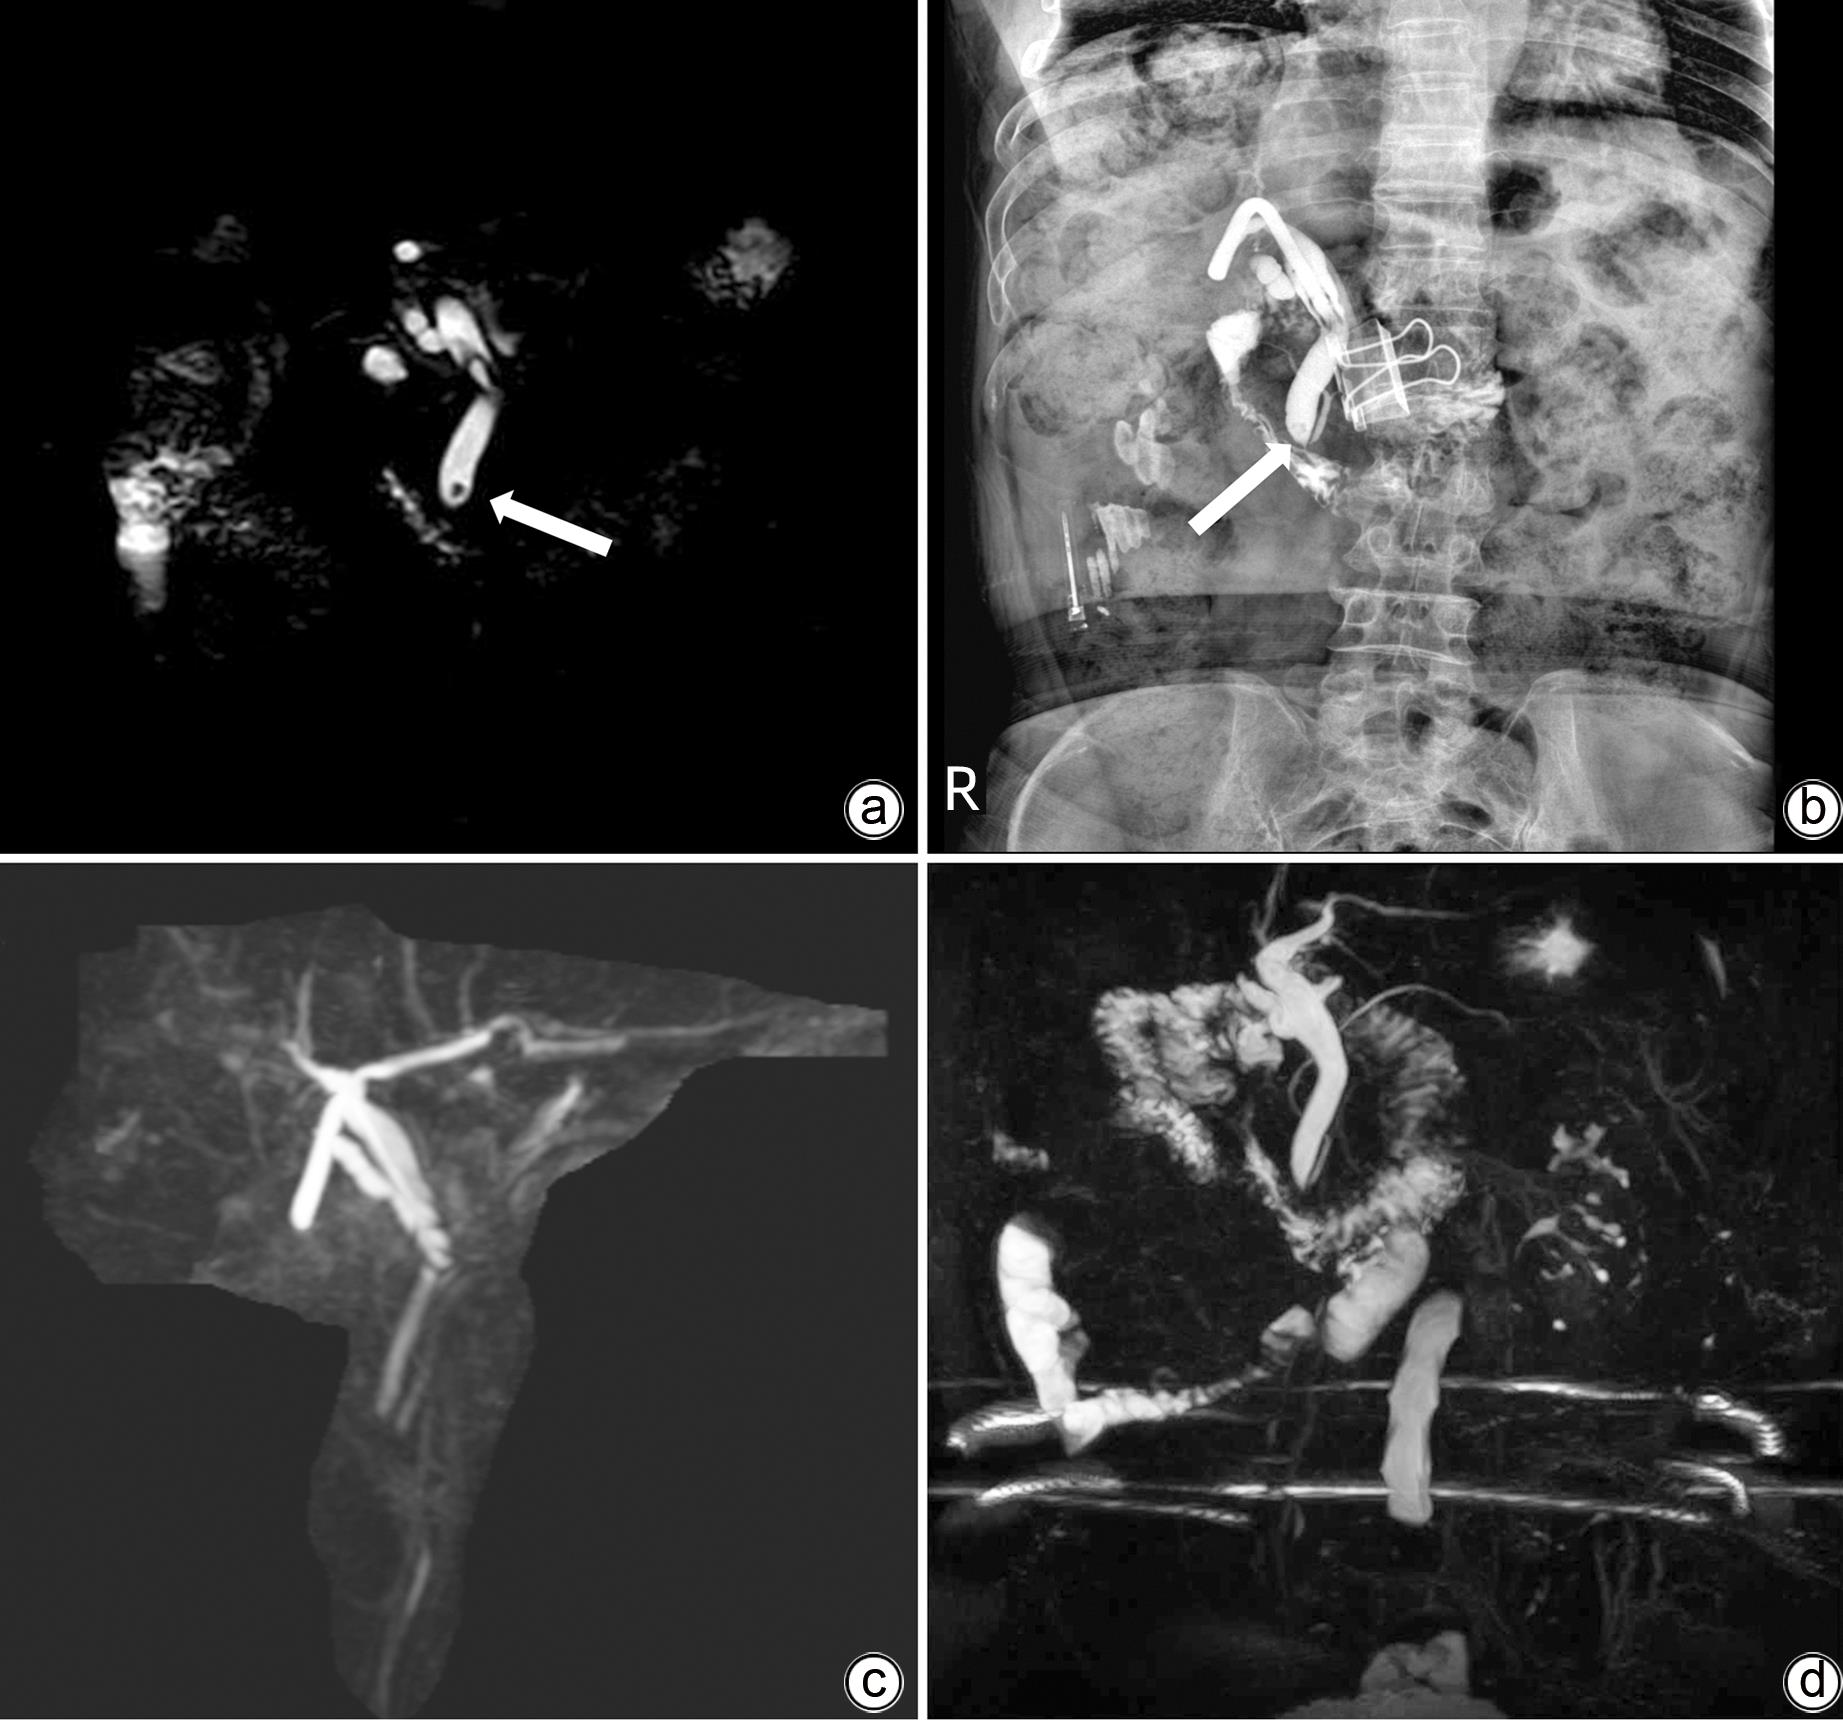

经T管输尿管软镜治疗胆总管残余结石1例报告

陈时红, 吴栋, 文洪, 陈元军, 曹刚

2023, 39(9): 2179-2184. DOI: 10.3969/j.issn.1001-5256.2023.09.022

摘要(960) HTML (273) PDF (989KB)(77)

摘要:

目前,对于术后胆总管残余结石的治疗,内镜逆行胰胆管造影(ERCP)和经T管窦道取石是主要的治疗手段,但以上治疗方法都存在一定的弊端,例如ERCP可能引起术后胰腺炎、出血、穿孔等并发症,T管窦道取石可能引起窦道损伤、窦道出血等。而输尿管软镜作为泌尿外科常用器械之一,具有直径小、角度灵活等特点,对于治疗胆总管结石具有良好的前景。贵州省第二人民医院普通外科应用输尿管软镜联合取石篮成功治疗胆总管结石1例,至今已随访7个月,患者无特殊不适,复查磁共振胰胆管成像检查未见胆总管结石。